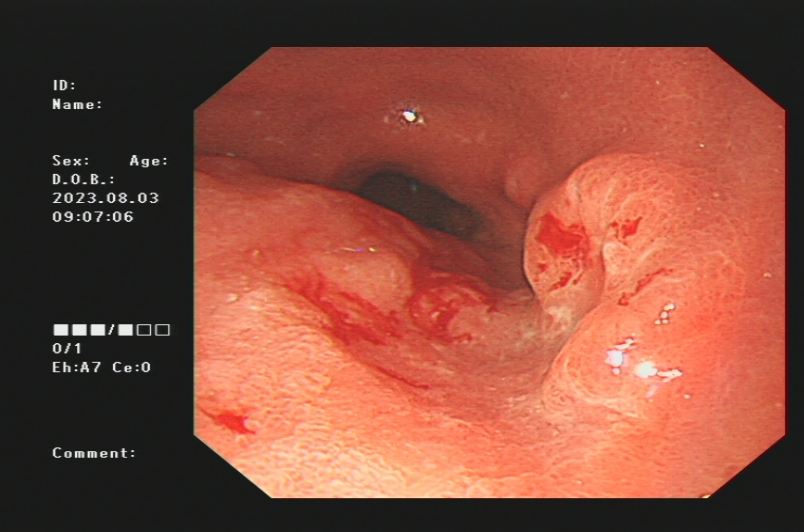

1.上消化道出血常见原因:消化性溃疡(胃溃疡、十二指肠溃疡)、食管炎、急性糜烂出血性胃炎、上消化道肿瘤(食管癌、胃癌)、剧烈呕吐造成的食管贲门黏膜撕裂伤、肝硬化引起的食管胃底静脉曲张。以下是一些常见的上消化道出血内镜图片:

食管贲门黏膜撕裂出血